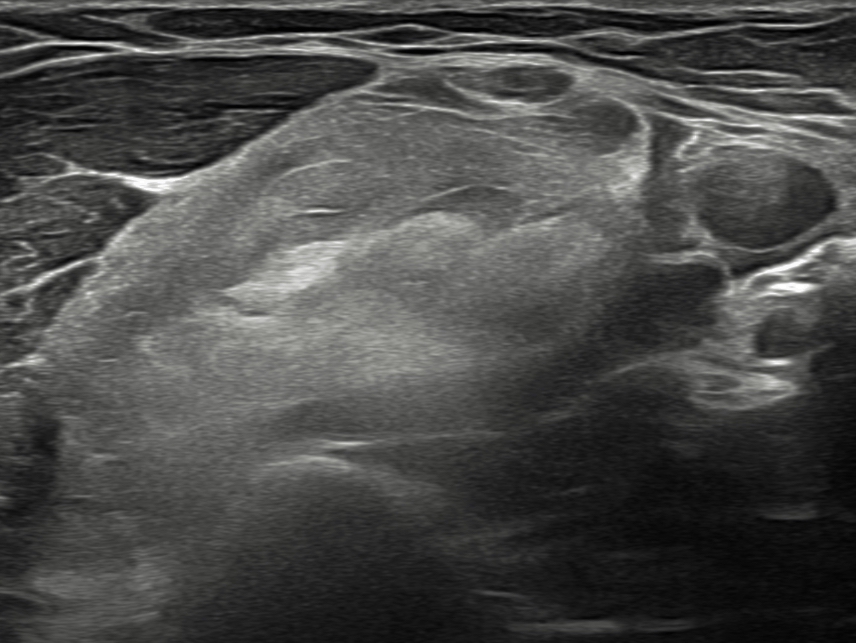

Con el objetivo de caracterizar la lesión, se realiza ecografía clínica.Hallazgos ecográficos

Se objetiva masa bien delimitada, heterogénea, con áreas hipoecogénicas y anecoicas en su interior, de aproximadamente 8 × 2 cm. La lesión parece depender del músculo coracobraquial y no muestra vascularización al Doppler.